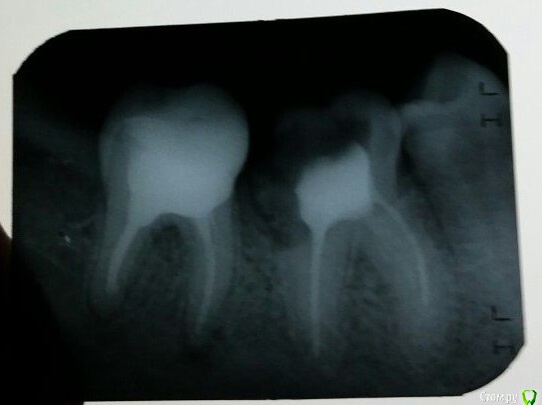

Lomator Опубликовано 1 октября, 2015 Поделиться Опубликовано 1 октября, 2015 Доброй ночи. Проблема возникла недели 2 назад, не с того не с сего резко заболел зуб утром (пищу этим утром вообще никакую не употреблял). Такая боль продолжалась дня 3, десна так же болела. Спустя неделю боль ушла, но при ударе зуба чувствуется в нём неприятная боль. Этот зуб уже лечился года 2-3 назад, его полностью расверлили и чем-то залили (не знаю наименование вещства). Рядом с этим зубом располагается "расколотый" сосед, дырка в котором образовалась, наверно, года полтора назад. Но т.к. я был в армии, никто не собирался брать его лечить и ставить какую-нибудь пломбу. Теперь к проблеме, пришёл в стоматологию, сказали не знают почему болит зуб. Он полностью запломбирован в каналах и они ничего не смогут с ним сделать, выдвинули версию, что возможно из-за соседнего, с дыркой, происходит боль, предложили придти запломбировать его. Никто не подскажет, с чем может быть ещё связана эта боль? Ведь 2 года зуб не подавал никаких болей, а тут резко начал мучать. Болит зуб крайний левый на фото, с дыркой соотвественно тот, что правее идёт. Ссылка на комментарий

St. Опубликовано 1 октября, 2015 Поделиться Опубликовано 1 октября, 2015 На корнях последнего зуба - воспаление. Сейчас оно обострилось - отсюда припухшая десна и боль при постукивании. Нужно перелечивать каналы в этом зубе. предложили придти запломбировать его На него коронку надо, как и на тот, который сейчас беспокоит. 1 Ссылка на комментарий

IvanK Опубликовано 2 октября, 2015 Поделиться Опубликовано 2 октября, 2015 6ку я бы удалил 3 Ссылка на комментарий